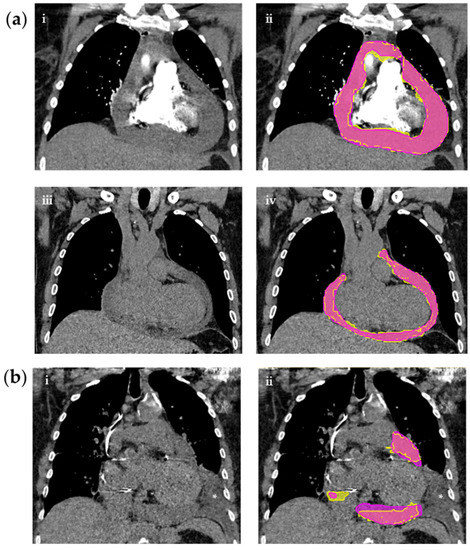

2.3. Segmentation